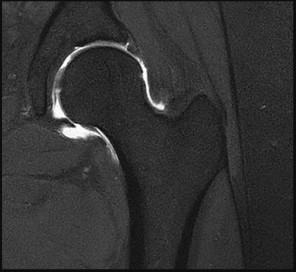

A 12-year-old obese male presents with left groin pain and an altered gait. Based on the presumed diagnosis of slipped capital femoral epiphysis (SCFE) shown in the representative radiograph, which of the following is the primary blood supply to the femoral head that is at highest risk for iatrogenic injury during percutaneous in situ pinning if the pin is placed in the posterosuperior quadrant?

The primary blood supply to the capital femoral epiphysis in children over the age of 3 is the posterosuperior retinacular vessels (lateral epiphyseal artery), which are terminal branches of the medial circumflex femoral artery (MCFA). During in situ pinning for SCFE, placement of the pin in the posterosuperior quadrant of the femoral neck/head places these extracapsular vessels at extreme risk of injury, potentially leading to avascular necrosis (AVN). Pins should ideally be placed in the center-center position to minimize this risk.